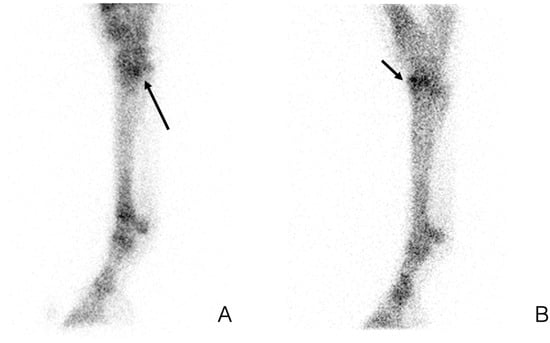

4. Indications of Positron Emission Tomography

4.4. PET for Longitudinal Monitoring of Lesions